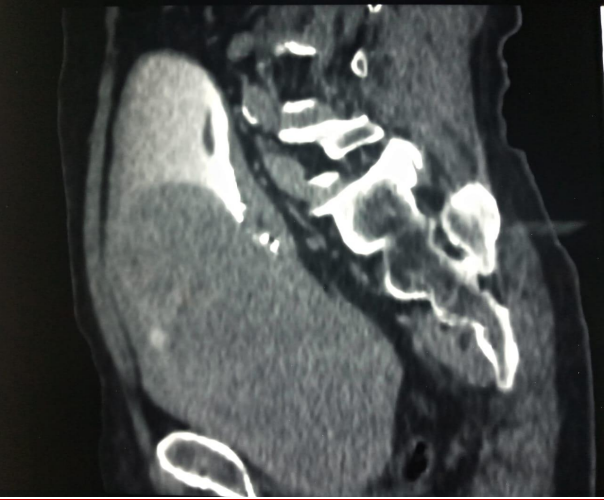

obstructive urinary symptoms, but had no hematuria or urinary incontinence. During physical evaluations, a firm  prostate with an unidentified border was detected through digital rectal examination due to its sizable volume. All laboratory tests came back normal except for total prostate-specific antigen, which registered at 10.9 ng/mL. Additionally, transrectal ultrasound measured the volume of the patient's prostate to be 250 mL. During the ultrasonography examination, a large prostatic mass was identified by the radiologist. This mass had caused displacement of the bladder towards its right side. Additionally, confirmation from the CT-scan revealed that indeed it was originating from prostate tissue (Figures 1 and 2).

Figure 1 and 2 Computed tomography scan showing the huge prostate filling the bladder.